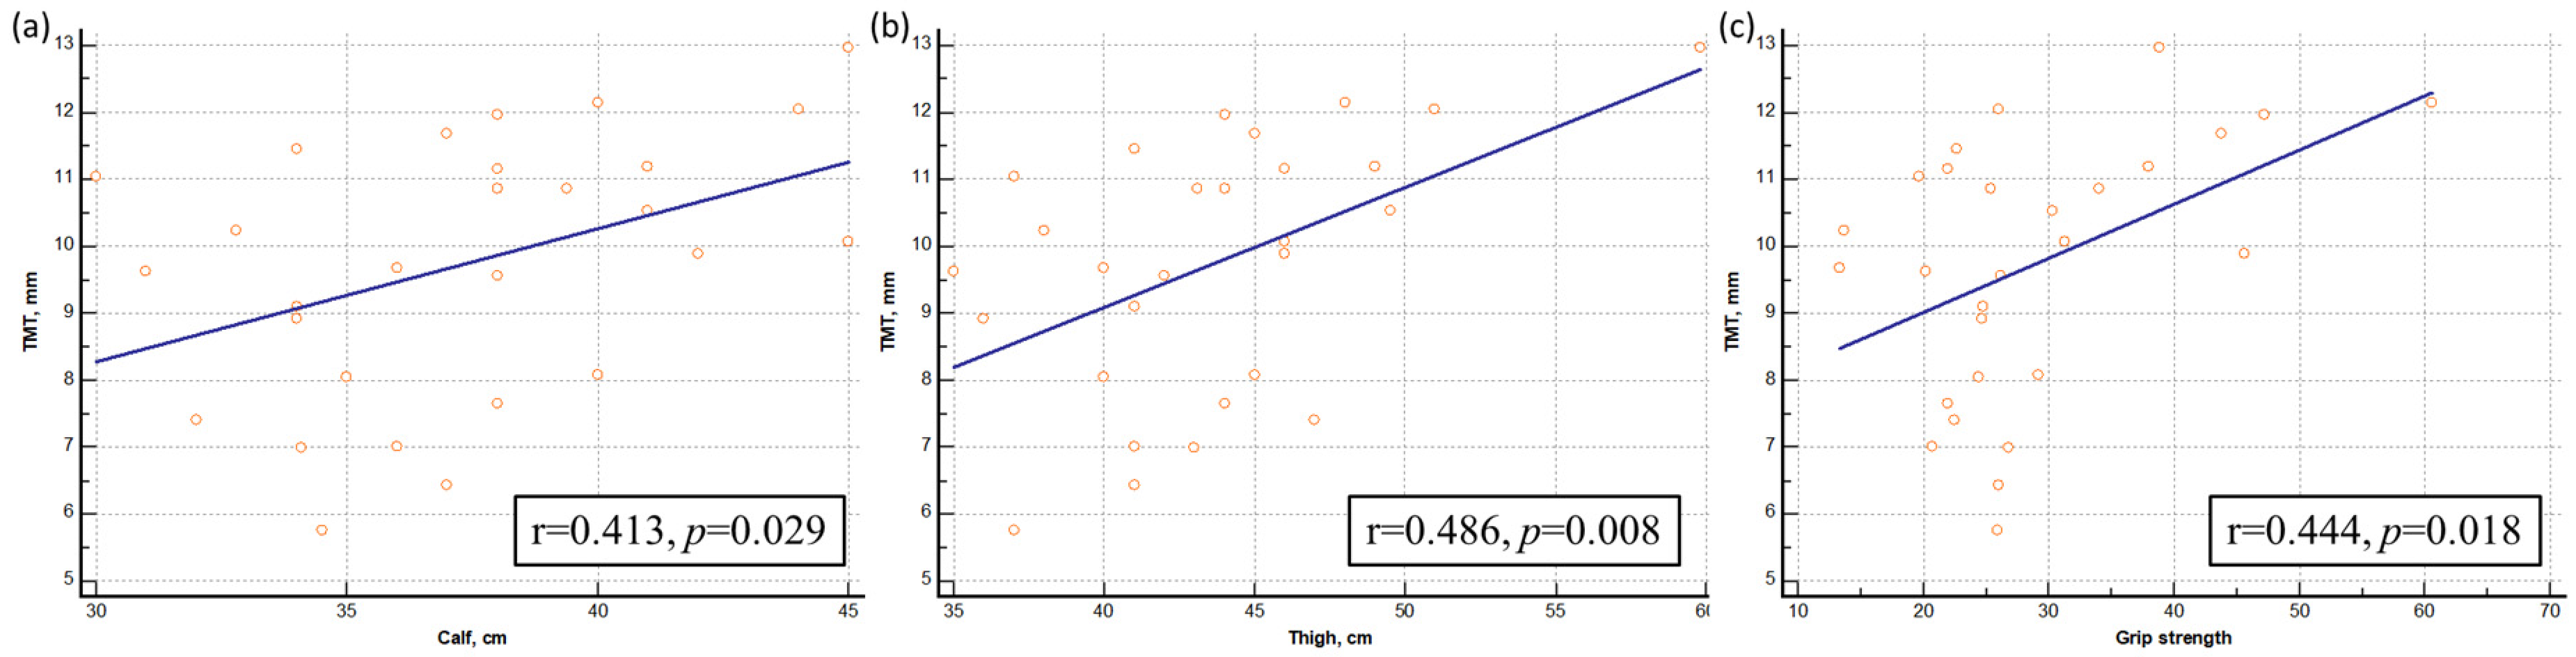

3.2. Correlation Analysis between Muscle Mass/Strength and TMT